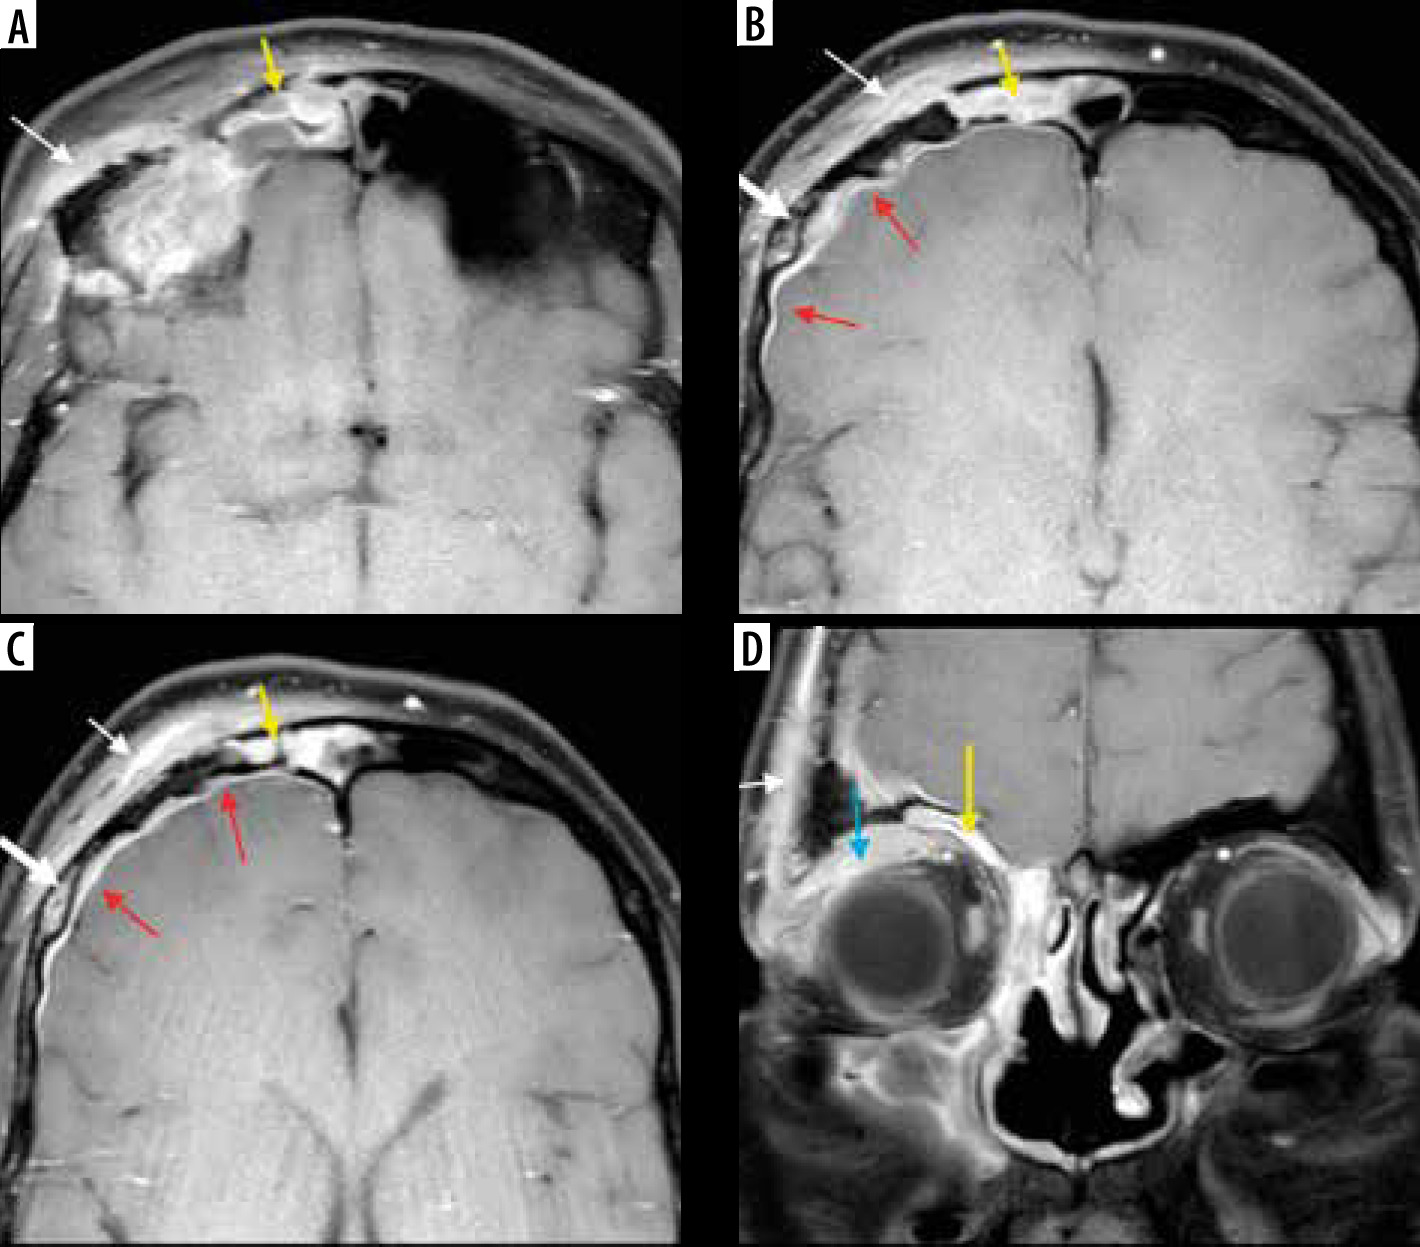

Frontal bone osteomyelitis in a patient with COVID-related right frontal mucormycosis. Axial (A-C) and coronal (D) post-contrast fat-suppressed (FS) T1-weighted (T1W) images demonstrate right frontal sinusitis (yellow arrows). The anterior and lateral aspects of the frontal bone demonstrate signal abnormality (thick white arrow) with an overlying enhancing subperiosteal collection on the right side (thin white arrows). Adjacent pachy-meningeal thickening, enhancement in the right frontal region (red arrows). Intra-orbital, extra-conal extension of the disease process noted along the supero-lateral aspect of the right orbit (blue arrow)

Figure 18